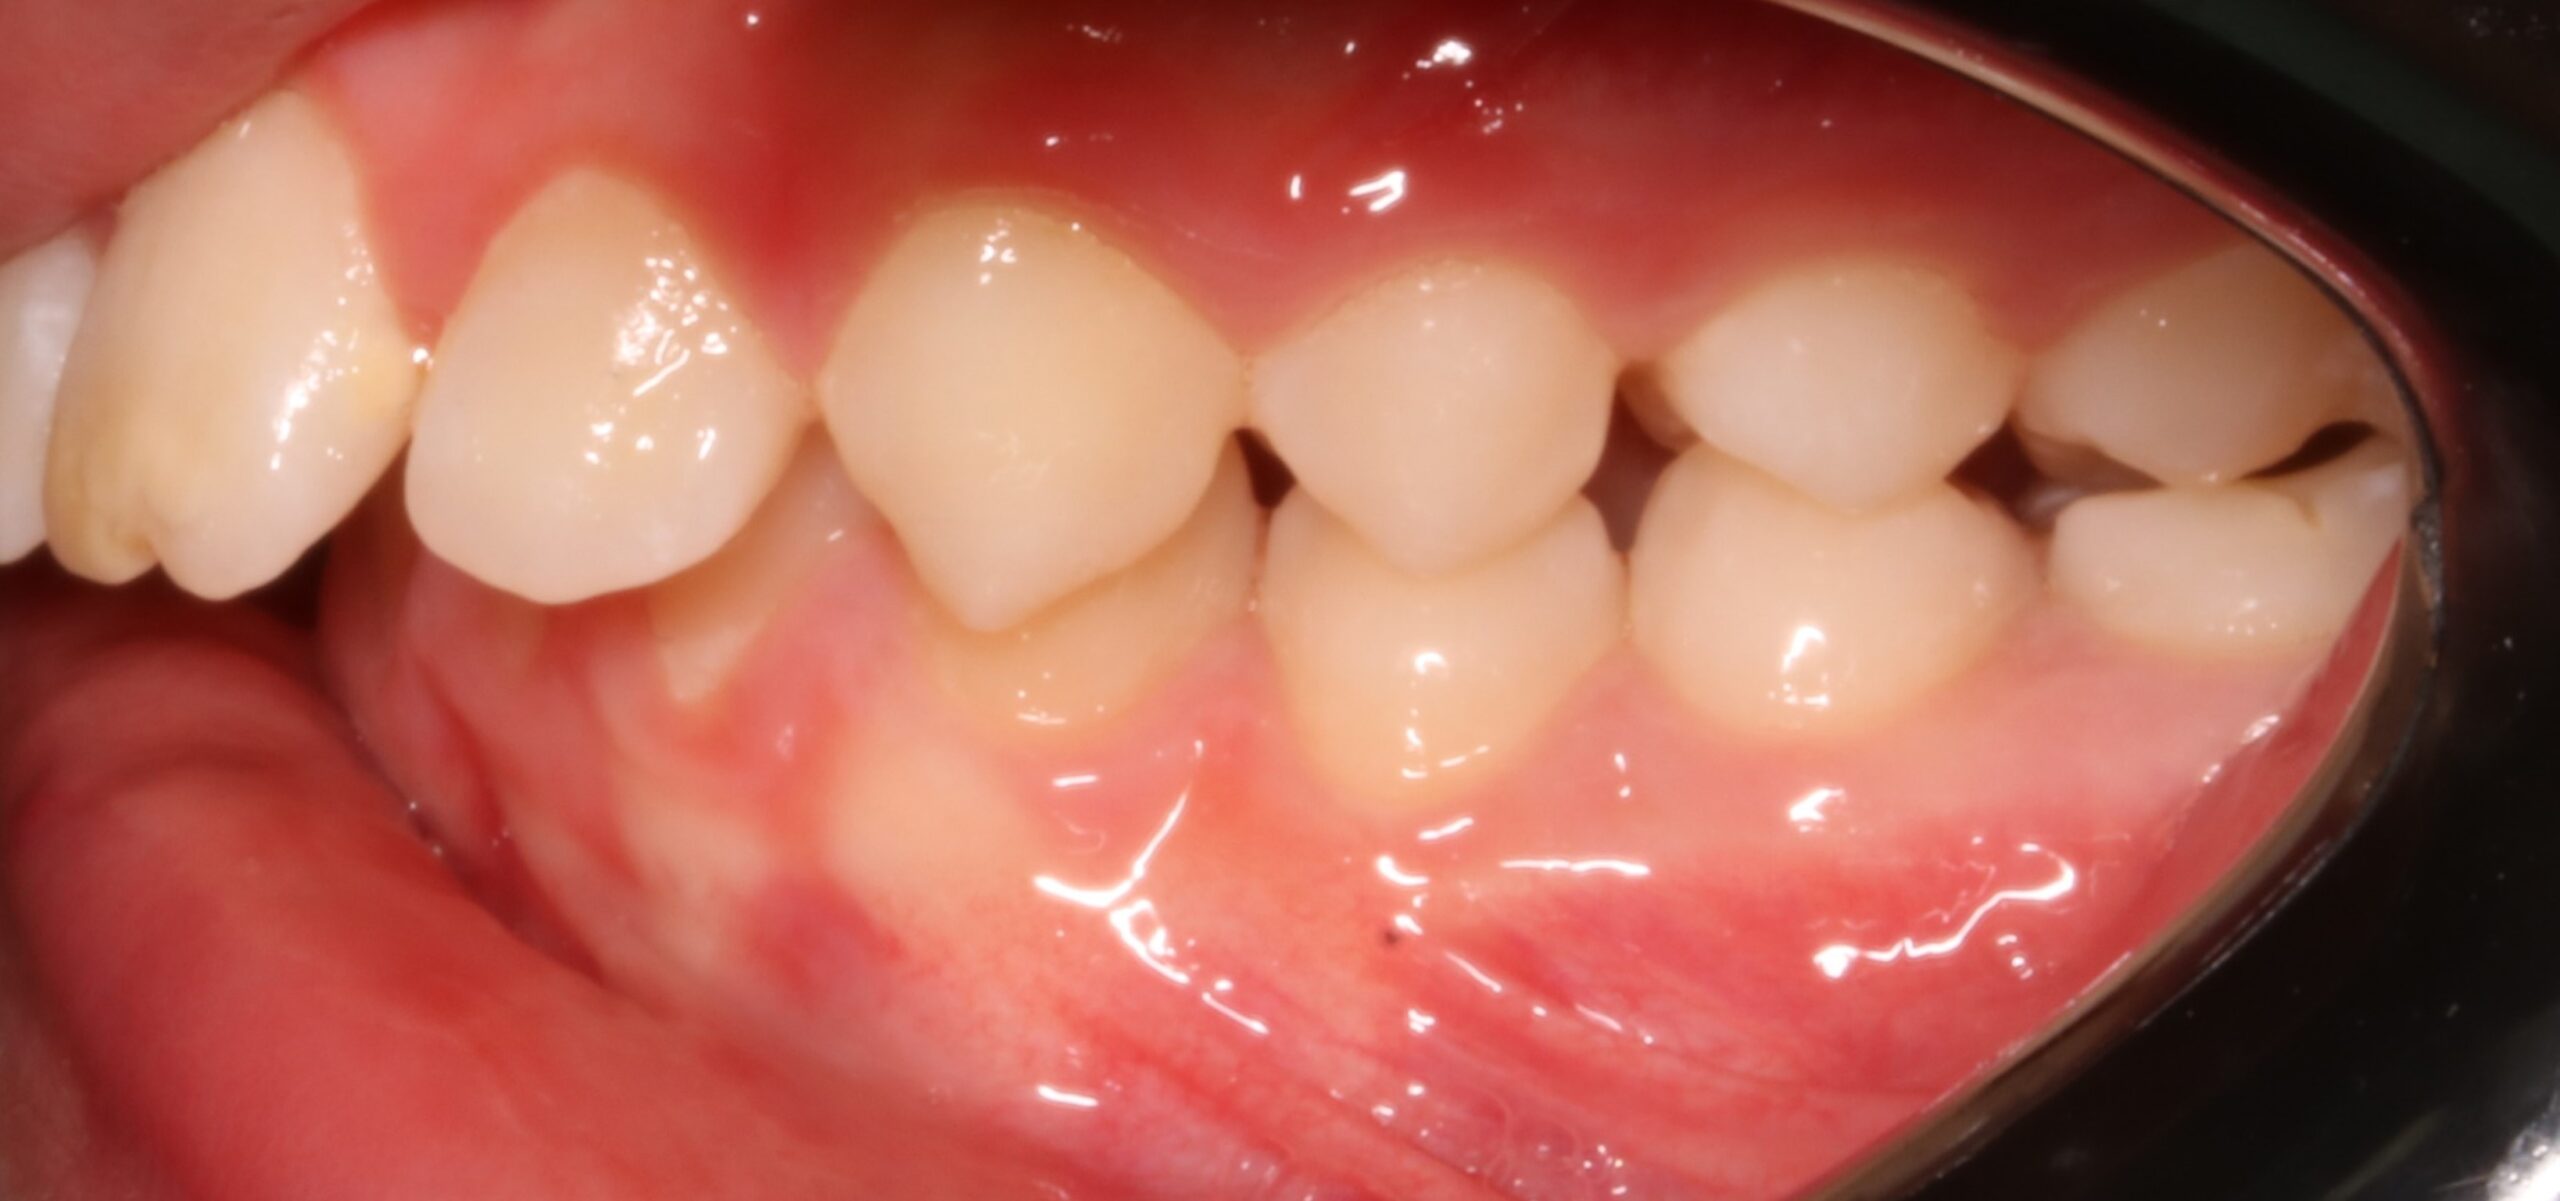

Nos encontramos con un caso en un timming adecuado para realizar un avance mandibular. También, nos favorece la inclinación el ángulo goniaco de 123 grados y la motivación del paciente. En contra nos perjudica la inclinación del incisivo inferior de 100 grados (lo podríamos controlar con microimplantes en la meseta inferior o alineadores, pero el paciente rechaza ambas opciones). Por otra parte,  en la radiografía frontal observamos un resto radicular en el 16, que decidimos extraer, y a petición del paciente, cerrar el espacio con mesialización del 17.

CLASE II MOLAR Y CANINA BILATERAL CON PERFIL DE MANDÍBULA RETRUSIVA AVANCE MANDIBULAR (CAMBIOS A NIVEL FACIAL+ CLASE I MOLAR Y CANINA)

-¿Cuál sería el paciente ideal? El paciente con un ángulo goniaco favorable, braquifacial, inclinaciones con Incisvo superior protruido, e incisivo retruido, y donde el paciente es colaborador.

De hecho, según el ángulo Co-Go-Me, aquellos pacientes con un ángulo menor a 125,5 serán pacientes favorables para realizar una ortopedia de clase II , mientras  que aquellos pacientes con un ángulo mandibular mayor serán candidatos para realizar control vertical. De hecho, los pacientes con un ángulo mayor a 128 grados, tienen un desarrollo mandibular de 4,2mm, y aquellos con un ángulo menor a 123, tendrán una cantidad de crecimiento mandibular  de 7,3mm. Por lo tanto deducimos, que a mayor ángulo goniaco, habrá un menor crecimiento mandibular.